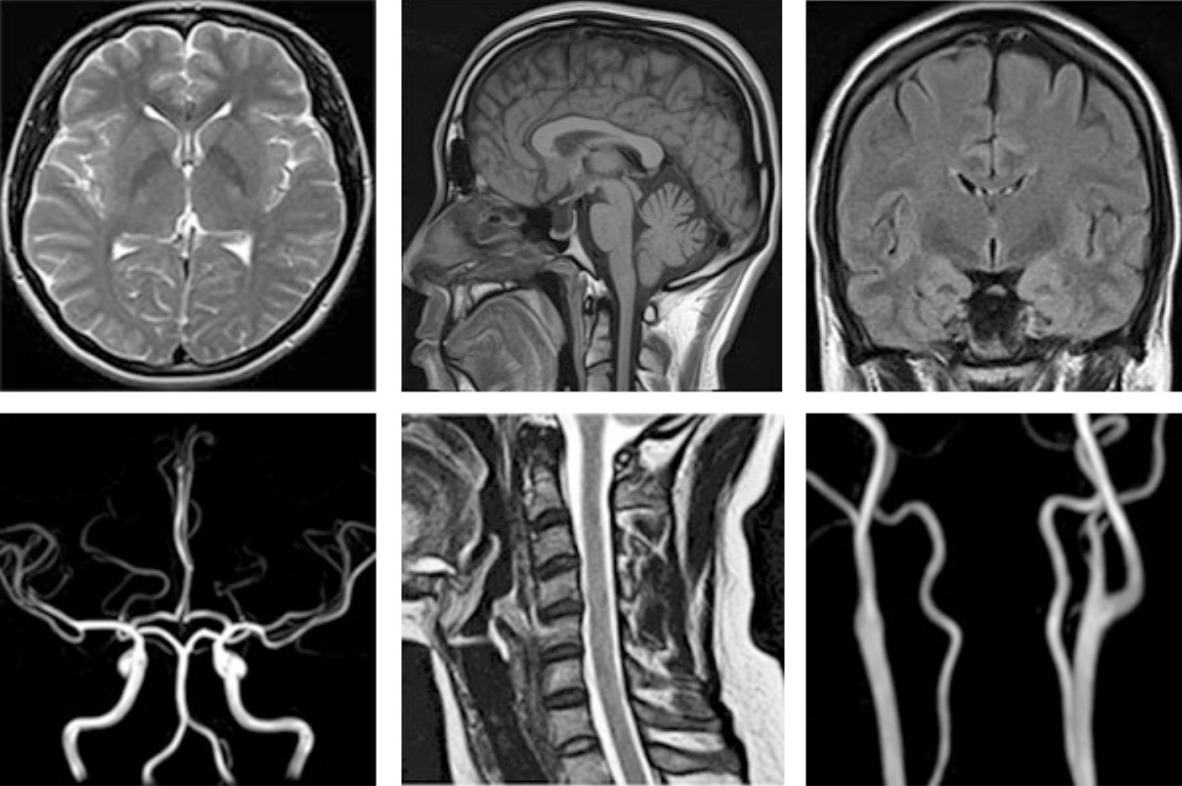

뇌 MRI 검사는 뇌혈관질환, 뇌종양, 뇌출혈, 신경학적 이상 증상 등을 평가할 때 필수적으로 활용되는 정밀 진단 장비이며, 강한 자기장을 이용해 인체 내부를 고해상도로 촬영하는 방식입니다. 최근 두통, 어지럼, 이상감각, 시야 흐림 등 다양한 증상에서 MRI 검사가 권고되는 사례가 증가하면서 많은 분들이 검사 비용, 촬영 시간, 조영제 여부에 따른 금식 필요성 등을 궁금해합니다.

MRI는 CT와 달리 촬영 시간이 길고, 장비 구조상 소음이 발생하며 금속 제거가 필수적입니다. 검사 시간은 촬영 방식에 따라 달라지며 일반적으로 30~50분이 소요됩니다.

- 뇌 MRI 단독: 30~50분

- 장비 성능이 높을수록 촬영 시간 단축 가능